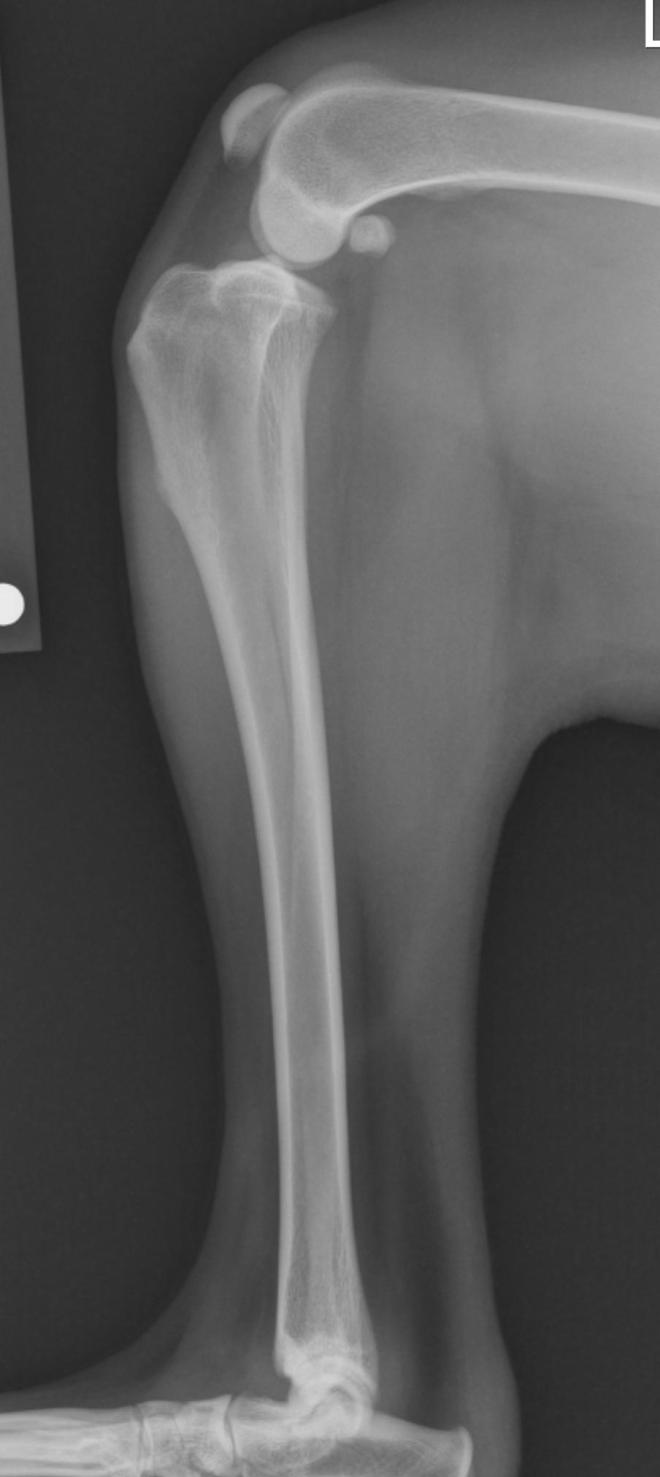

Radiographs: Classic radiographic findings are joint swelling, arthritic change and subluxation (forward movement) of the tibia in relation to the femoral. Classic areas of arthritic development are the patella, fabella, tibial plateau and femoral condylar ridges. I recommend the radiograph (x-ray) be taken with the knee and hock in 90 degree flexion. Please note the differences of the normal and affected knee in the radiographs attached. The benefit of radiographs for me is to see mild changes to confirm the diagnosis and to derive my measurements for either the tibial plateau leveling osteotomy (TPLO) or tibial tuberosity advancement (TTA) procedures.

X-ray of stifle with a ruptured ACL

X-ray of a normal knee